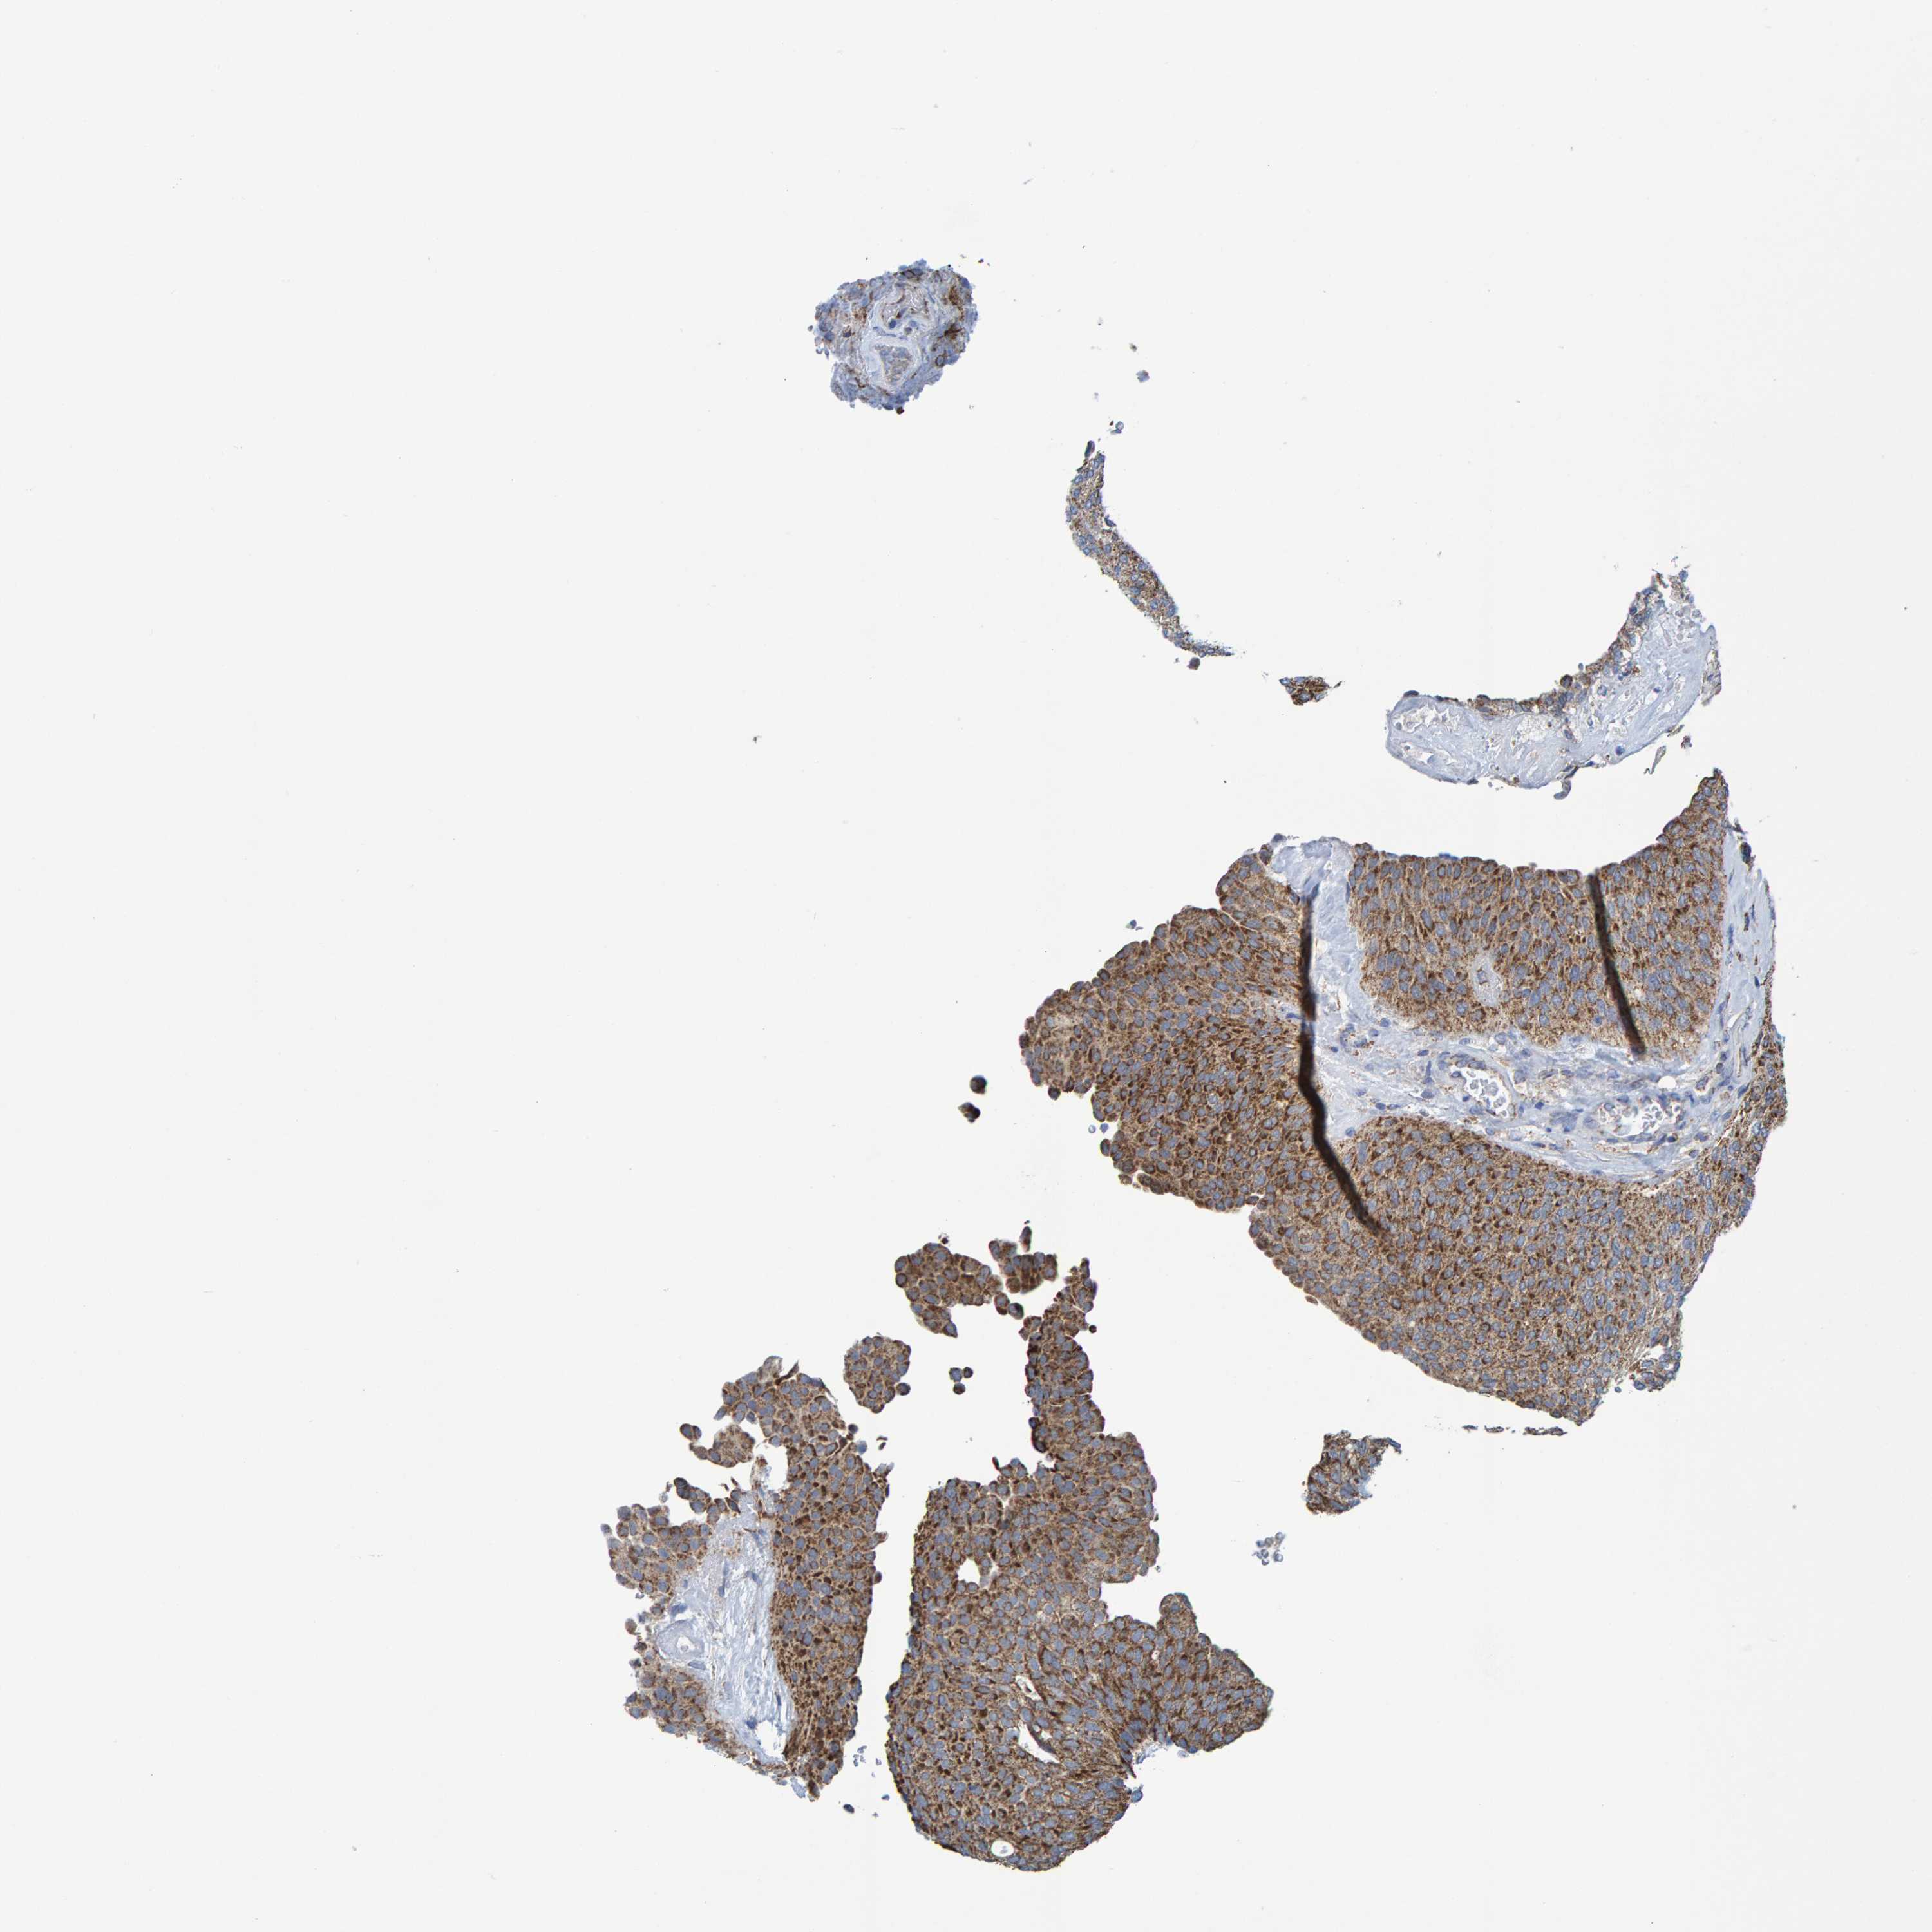

UROTHELIAL CANCER - Protein expressioni

A mouse-over function shows sample information and annotation data. Click on an image to view it in a full screen mode. Samples can be filtered based on level of antibody staining by selecting one or several of the following categories: high, medium, low and not detected. The assay and annotation is described here.

Note that samples used for immunohistochemistry by the Human Protein Atlas do not correspond to samples in the TCGA dataset.

Antibody stainingi

Antibody staining in the annotated cell types in the current human tissue is reported as not detected, low, medium, or high, based on conventional immunohistochemistry profiling in selected tissues. This score is based on the combination of the staining intensity and fraction of stained cells.

Each image is clickable and will lead to virtual microscopy that enables deeper exploration of all samples and also displays staining intensity scores, fraction scores and subcellular localization as well as patient and tissue information for each sample.

Antibody HPA022522

Antibody HPA023007

Urothelial carcinoma, Low grade

Urothelial carcinoma, High grade